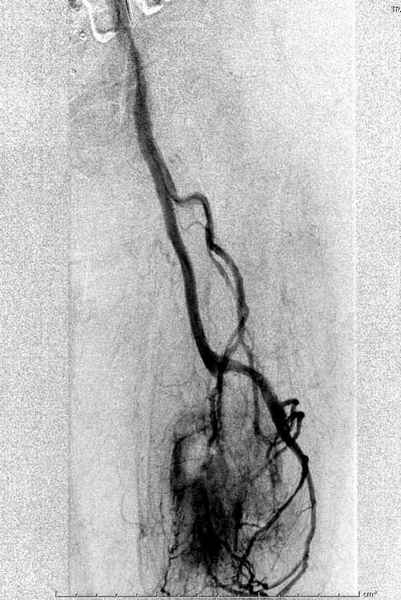

Для предупреждения кровотечения во время рассверливания, за день до операции провели эмболизацию сосудов питающий метастаз. http://radiology.rsnajnls.org/cgi/reprint/150/3/673.pdf (7-11, 12-15-16)

С минимальным рассверливанием и ретроградным методом провели остеосинтез бедра 12 мм гвоздем. (17-20)

Кровопотеря во время операции меньше 100 мл.